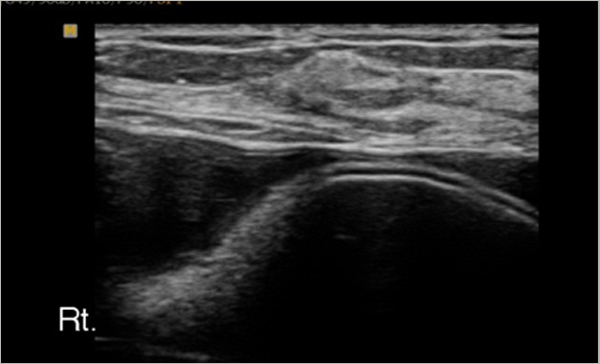

2) ¼ö¼úÈÄ 1-2³â¸¶´Ù À¯¹æÃÊÀ½ÆÄ¸¦ ÇÏ¿©¼ º¸Çü¹°ÀÇ ¹Ì¼¼ÇÑ ´©ÃâÀÌ ÀÖ´ÂÁö È®ÀÎÇÑ´Ù.